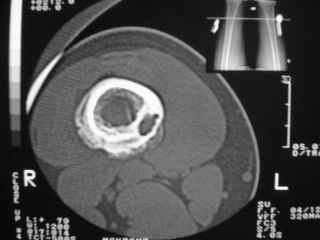

Здравствуйте, уважаемые коллеги!Представляю вашему вниманию интересный случай и пока что непонятный для меня в диагностическом плане. На днях в наше отделение (детской ортопедии и травматологии) поступил 13-летний мальчик по направлению из поликлиники с диагнозом: остеома нижней трети правого бедра.

Анамнез практически никакой: в следствие травмы (растяжение связок коленного сустава) от 07.11.2004 выполнены Rg-граммы в травмпункте и обнаружено опухолевидное образование. Первичные Rg-граммы я не публикую, так как они заметно худшего качества, да и динамики за прошедшие три недели не отражают. Болевой синдром купирован в течение трёх дней. В настоящий момент мальчика ничего не беспокоит. Ходьба не нарушена, опухоль пальпируется с трудом по задней поверхности в н\3 правого бедра, пальпация безболезненна, объем движений в суставах правой нижней конечности полный и симметричный. Кожа над опухолью не изменена.В нашей клинике проведено дополнительное обследование: общие анализы крови и мочи, биохимия крови без особенностей. Выполнены Rg-граммы на цифровом Siemens обычные и продольные томограммы срезами 3-5 мм, а также компьютерная томография поперечными срезами по 5 мм. Прошу обратить внимание, что на приведённых томограммах видны две полости 10х15 мм и 15х60 мм. Также имеются два опухолевидных образований наслаивающихся друг на друга: уплощённое и вытянутое 10х100 мм и элипсовидной формы 15х30 мм. Это хорошо заметно на фото a_1.jpg c_1.jpg и d_1.jpg. Плотность внутри полостей 125% от плотности костномозгового канала, плотность наружного опухолевидного образования 55% от плотности кортикального слоя. Также отмечается линия перелома по центру наружного опухолевидного образования.Исходя из полученных данных мнения в плане диагноза несколько разделились от 1)сочетания кортикальной фиброзной дисплазии и латентно протекавшего маршевого перелома н\3 правого бедра до 2)остеосаркомы. В отношении первого варианта не сходится отсутствие клиники при переломе такой крупной кости как бедро, второй вариант вообще оставлю без комментария, ибо некомпетентен. Хотелось бы услышать мнения коллег, с удовольствием ознакомлюсь с любыми предположениями и замечаниями.С уважением, Александр Е. КлоковОтделение детской ортопедии и травматологииБСМП г. Мурманска.